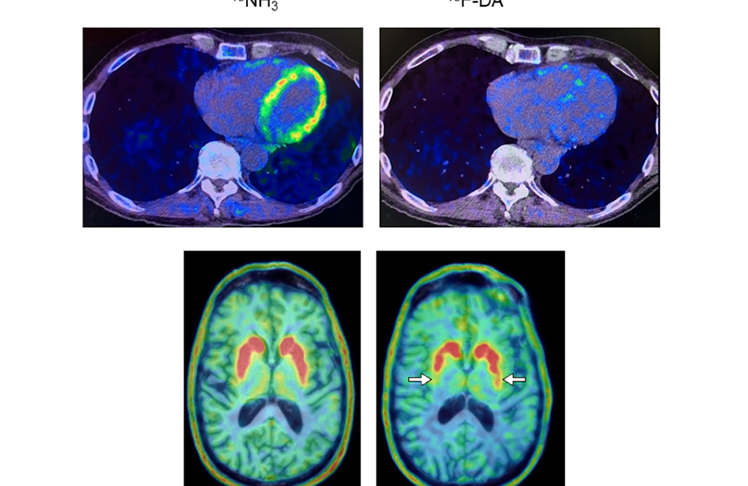

The research took place at the NIH Clinical Center; currently the sole facility offering 18F-dopamine PET scanning. PET scans employ a radioactive tracer to visualize metabolic or biochemical processes within body organs.

The new study, led by Dr. Goldstein, found that people who were at risk and had low 18F-dopamine-derived radioactivity in the heart were much more likely to develop Parkinson’s or Lewy body dementia over time than people who had the same risk factors but normal radioactivity.

Eight of the nine participants who had lower cardiac 18F-dopamine-derived radioactivity on their first scan were later diagnosed with Parkinson’s disease or Lewy body dementia. Remarkably, only one of the eleven participants with normal initial radioactivity developed a central Lewy body disease. All nine participants who developed a Lewy body disease exhibited low radioactivity before or at the time of diagnosis.